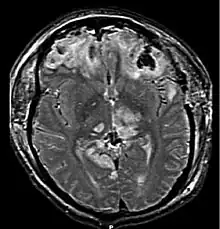

Brain herniation is a potentially deadly side effect of very high pressure within the skull that occurs when a part of the brain is squeezed across structures within the skull. The brain can shift across such structures as the falx cerebri, the tentorium cerebelli, and even through the foramen magnum (the hole in the base of the skull through which the spinal cord connects with the brain). Herniation can be caused by a number of factors that cause a mass effect and increase intracranial pressure (ICP): these include traumatic brain injury, intracranial hemorrhage, or brain tumor.[1]

Herniation can also occur in the absence of high ICP when mass lesions such as hematomas occur at the borders of brain compartments. In such cases local pressure is increased at the place where the herniation occurs, but this pressure is not transmitted to the rest of the brain, and therefore does not register as an increase in ICP.[2]

Because herniation puts extreme pressure on parts of the brain and thereby cuts off the blood supply to various parts of the brain, it is often fatal. Therefore, extreme measures are taken in hospital settings to prevent the condition by reducing intracranial pressure, or decompressing (draining) a hematoma which is putting local pressure on a part of the brain.

Treatment involves removal of the etiologic mass and decompressive craniectomy. Brain herniation can cause severe disability or death. In fact, when herniation is visible on a CT scan, the prognosis for a meaningful recovery of neurological function is poor.[2] The patient may become paralyzed on the same side as the lesion causing the pressure, or damage to parts of the brain caused by herniation may cause paralysis on the side opposite the lesion.[11] Damage to the midbrain, which contains the reticular activating network which regulates consciousness, will result in coma.[11] Damage to the cardio-respiratory centers in the medulla oblongata will cause respiratory arrest and (secondarily) cardiac arrest.[11] Investigation is underway regarding the use of neuroprotective agents during the prolonged post-traumatic period of brain hypersensitivity associated with the syndrome.[17]